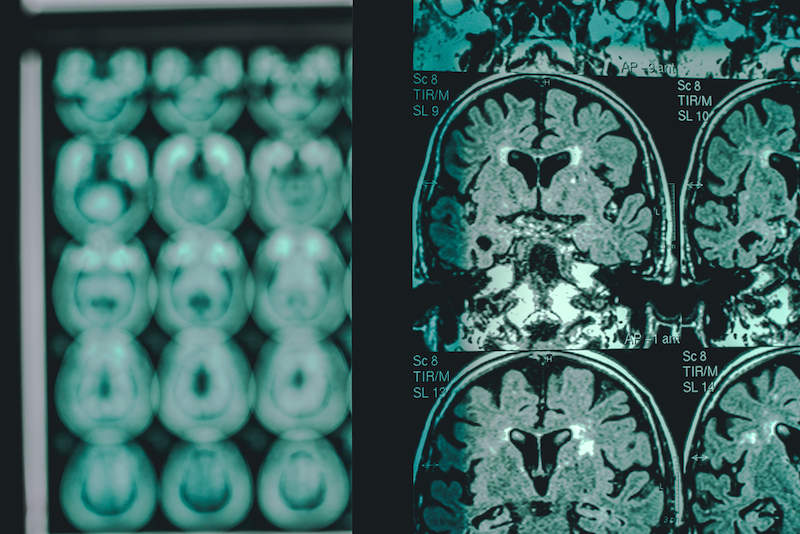

Today, the diagnosis of Alzheimer’s uses a combination of clinical assessments, psychological testing, and brain imaging techniques. Imaging is focused on two proteins related to Alzheimer’s disease — amyloid beta and tau. Amyloid beta is a protein that forms toxic plaques in the brain, a sign of Alzheimer’s. Advanced imaging techniques, such as positron emission tomography (PET) and amyloid-sensitive magnetic resonance imaging (MRI), can detect amyloid deposits, providing a window into the brain’s health. The second protein is tau, which creates tangles within neurons and cell death. Measuring tau levels in cerebrospinal fluid (CSF), the fluid that surrounds the brain and spinal cord, can aid in early diagnosis and predict disease progression. A recent human trial reported that amyloid beta levels were indicative of Alzheimer’s disease 18 years before the individual was diagnosed.

Amyloid beta and tau are the most commonly evaluated biomarkers. However, they’re not widely used because they require advanced imaging or CSF sampling which are expensive and/or invasive. Thus, it has been difficult to detect the disease early, when intervention and treatment could have the most significant impact. Fortunately, the field of Alzheimer’s research is constantly evolving, developing novel methods to identify the disease at its earliest stages. Evaluation techniques that are non-invasive and don’t require expensive equipment or expertise will have the greatest positive impact. Here’s a review of new approaches for early detection of Alzheimer’s disease.